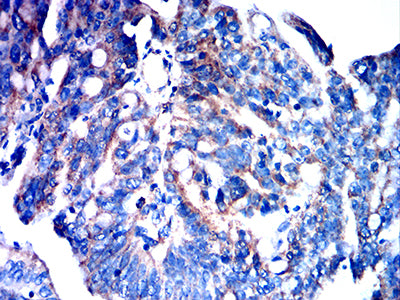

分类: 科研抗体货号: 32203别名: PBT; SCFR; C-Kit; CD117; MASTC应用: IF,FCM反应种属: Human